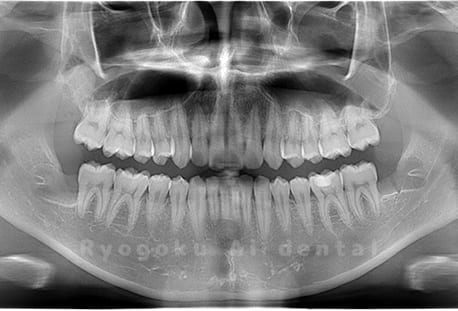

真っ直ぐ生えている親知らず

親知らずが真っ直ぐ生えているタイプです。

このタイプは真っ直ぐ生えていて咬み合わせに問題がなければ、抜歯しないケースもあります。ただし、虫歯になっていたり、痛みがあったり、咬み合わせが悪かったりすると抜歯をおすすめします。